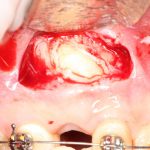

Конечно, мы можем удалить и зуб мудрости, и появившуюся из-за него фолликулярную кисту. Такая операция занимает, максимум, 20-25 минут:

Но по сложности это вмешательство выше, чем просто удаление ретинированного зуба, а по времени — дольше (удаление такого зуба, как на первом снимке, занимает 10-15 минут). Я уже не говорю о возможных рисках — несомненно, простое удаление ретинированного зуба мудрости более безопасно, нежели удаление ретинированного зуба с развившейся фолликулярной кистой.

Следовательно, удали мы этот зуб мудрости раньше — меньше было бы возни, меньше проблем во время и дискомфорта после операции.

Кстати, забыл добавить, что использование биоматериалов для «заполнения полости кисты» — это способ развести пациентов на дополнительные расходы. Никакой другой цели использования графтов при подобных вмешательствах, лично я не вижу.